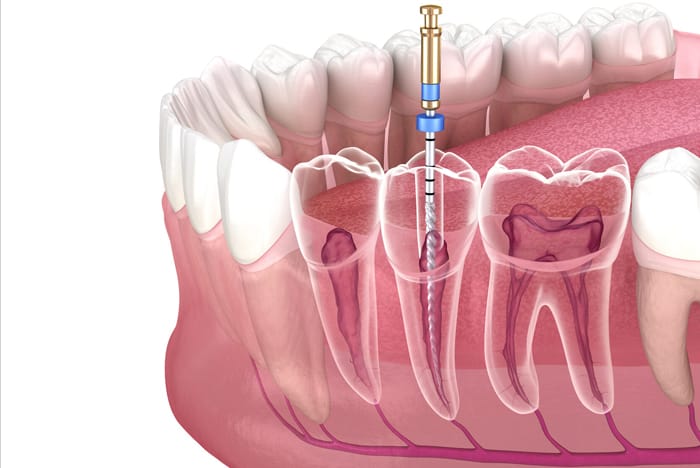

O tratamento de canal bem explicado,como você nunca viu Quando falamos em tratamento de canal, muitas pessoas ainda associam o...